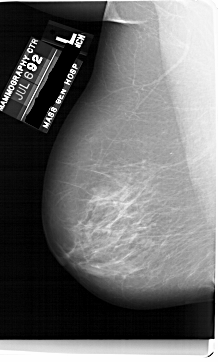

A_1749_1.RIGHT_MLO

RIGHT_MLO LINES 6616 PIXELS_PER_LINE 3631 BITS_PER_PIXEL 12 RESOLUTION 43.5 OVERLAY